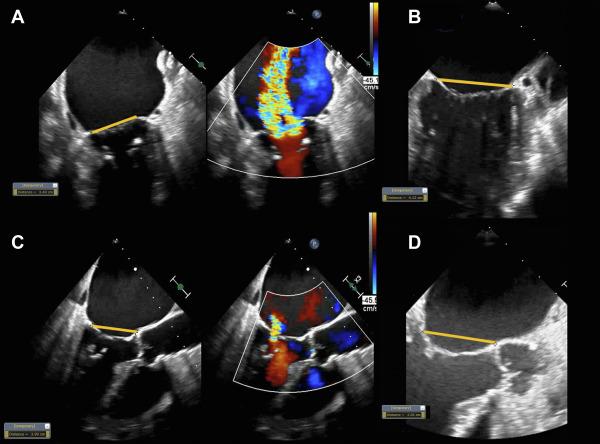

STEMI-DTU trial: Delayed reperfusion with LV unloading shows no significant benefit over immediate PCI, though a potentially offsetting protective effect of the pump warrants further